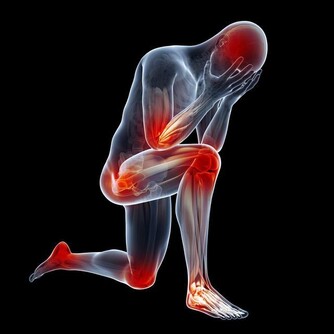

長期疲勞

經常性感到無來由的疲勞感,即可能是皮質醇水平過高的徵兆。